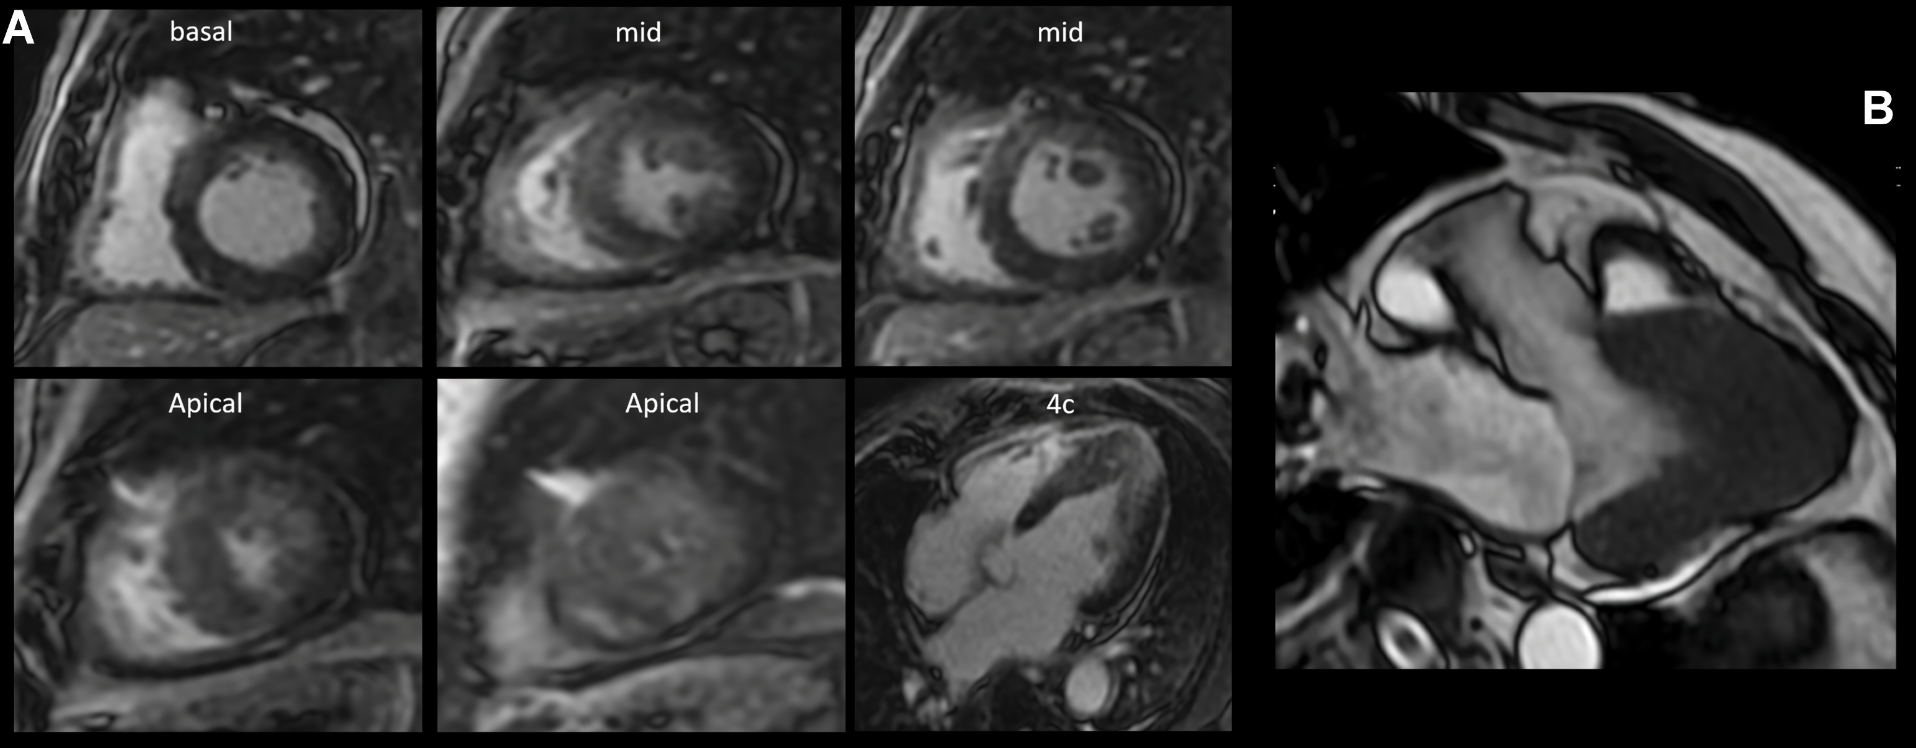

Intramyocardial enhancement was observed in the apical third with an anterior, inferior lateral and septal patchy-diffuse pattern, all compatible with apical hypertrophic cardiomyopathy with preserved biventricular function and a non-ischemic myocardial enhancement pattern, suggestive of diffuse fibrosis in hypertrophic areas of the left ventricle, with a semiquantitative calculation of LV myocardial fibrosis of 52% (Figure 2A). The 3-chamber magnetic resonance (MRI) imaging slice showed a left ventricle (LV) with an end-diastolic volume (EDV) of 63 ml and an end-systole volume (ESV) of 23 ml, with a sign of "ace of spades" due to collapse in systole in the apical third of the ventricle with a maximum thickening at the apical level of 23 mm (Figure 2B). It was decided to perform a left heart catheterization due to electrocardiographic findings and episodes of ventricular tachycardia; this showed coronary arteries without lesions. Due to findings in the stress test of VT and high load of diffuse fibrosis in hypertrophic areas in the MRI, it was decided to take the patient to an electrophysiological study to determine the origin of the arrhythmia and substrate arrhythmic modulation through three-dimensional electroanatomical mapping system. With identification of PVC and focal VT from the mitral postero-septal papillary muscle (Figure 3A), so radiofrequency ablation was performed successfully (Figure 3B). Subsequently, it was decided to place a definitive percutaneous bicameral cardiodesfibrillator to prevent sudden death. The patient tolerated the procedure without complications and was prescribed amiodarone 200 mg orally daily during 3 months. Studies for Fabry disease were requested which were negative, and a panel for MYH7, TNNI3, GLA, MYBPC3, TNNT2, TPM1, MYL2, MYL3, LAMP3, LSAMP, PRKAG2, АСТАА1 gene mutations with negative result.

Figure 2. (A):  Inversion-recovery sequence after intravenous contrast administration, enhancement was observed at 10 minutes. Basal third: intramyocardial septal. Middle third: Intramyocardial septal. Apical third: Intramyocardial in anterior, lateral, inferior and septal diffuse-patches. (B): Left ventricular 3-chamber view with a diastolic diameter of 50 mm, systolic diameter of 30 mm, Ace of Spades signs due to collapse in systole in the apical third of the LV. LV measurements at apical level with septal thickness of 18 mm, anterior wall 20 mm, lateral wall 23 mm and inferior wall 16 mm